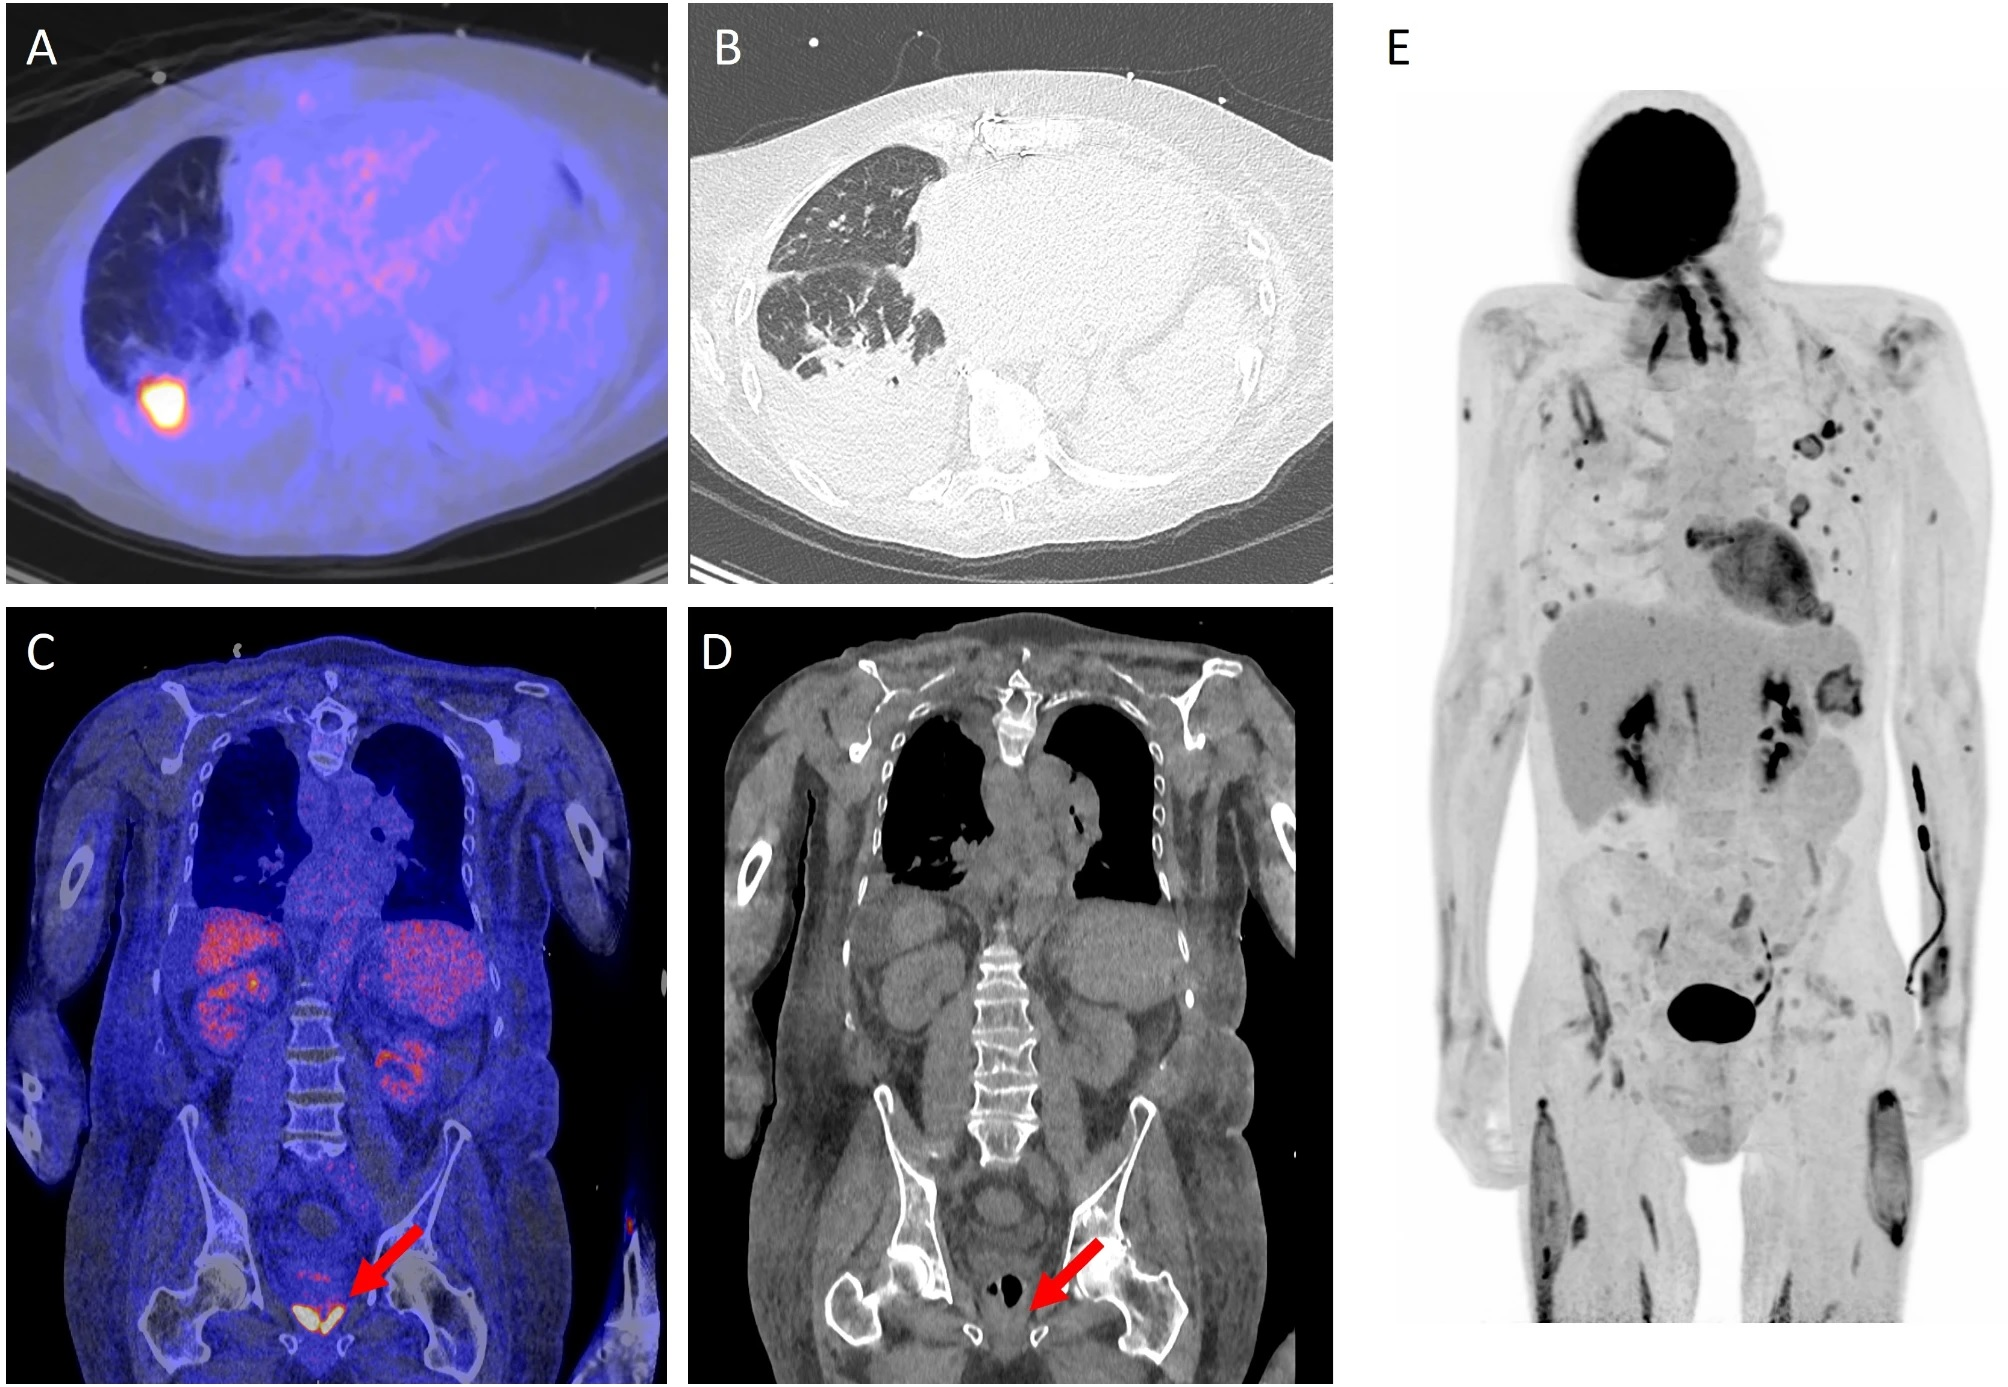

A 68-year-old woman who met the FUO criteria. F-18 FDG-PET/CT torso imaging shows longitudinal uptake along the aorta and the large vessels, pathognomonic for giant cell arteritis (arrows). The patient showed only minimal clinical symptoms for vasculitis. Causal anti-inflammatory therapy with oral cortisone was started, to which patient responded well. Image courtesy of Scientific Reports.The largest part of final diagnoses was assorted to infectious diseases (109/300 patients, 36.3%) followed by autoimmune/rheumatic diseases (51/300 patients, 17%) and malignancy (33/300 patients, 11%), according to the findings.